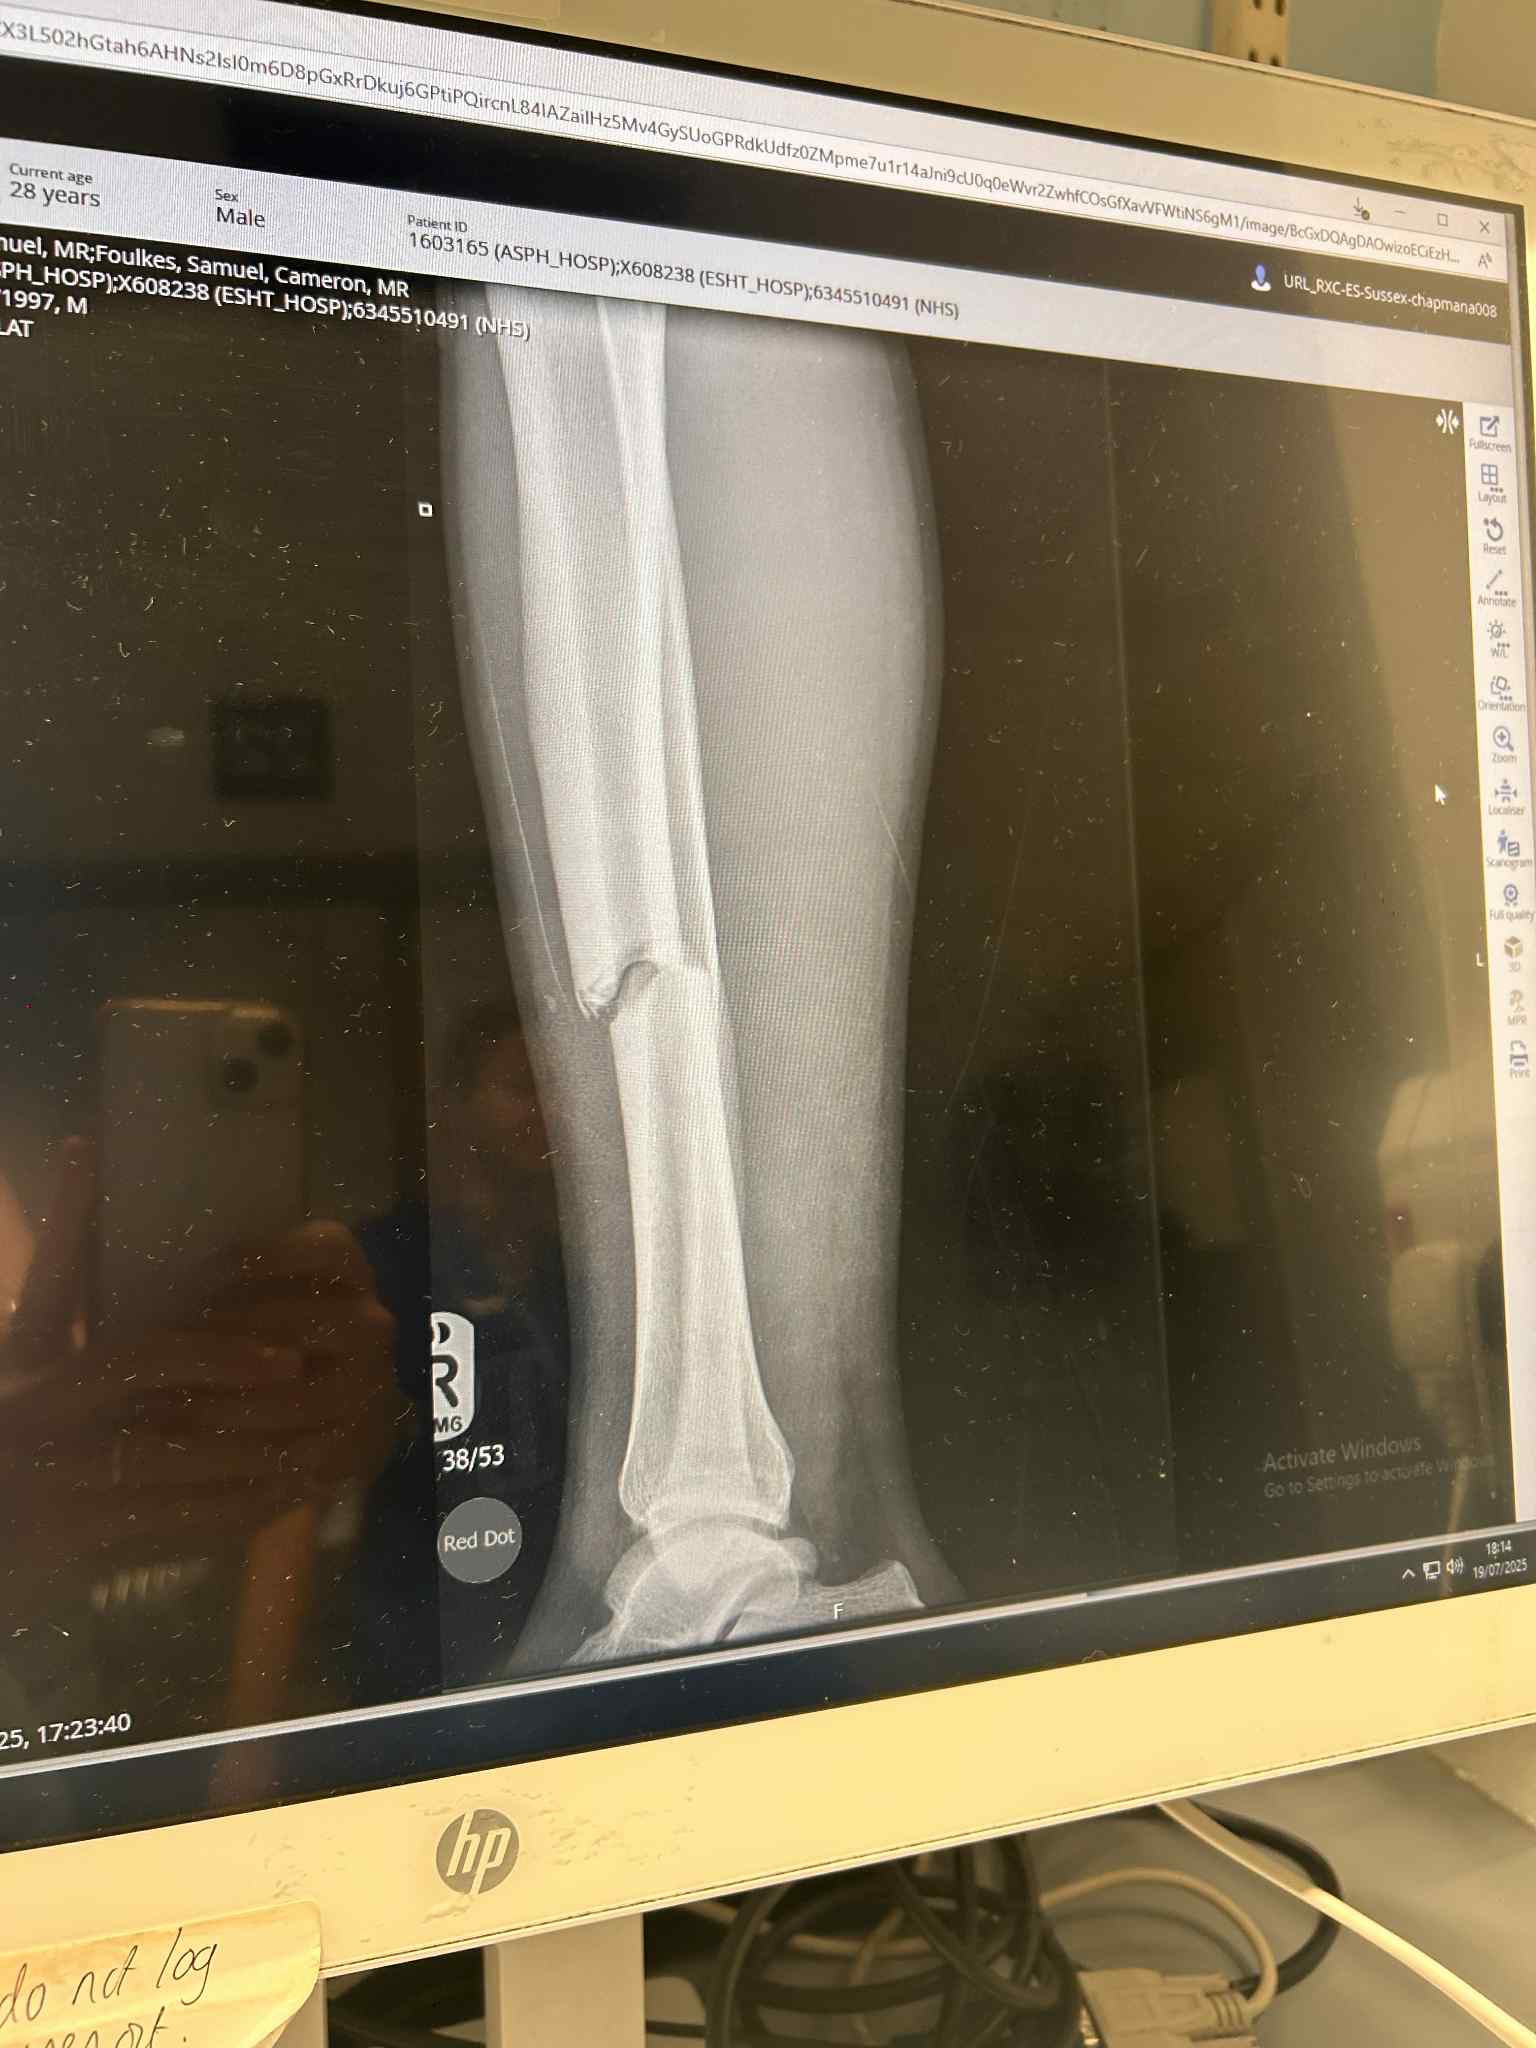

Unfortunately Sammy Foulkes suffered a broken Tibia today playing a pre-season friendly for Rye Town FC.

Sammy is due to have surgery tomorrow and will have a long road of recovery ahead, and being self employed we would like to try and make things a little easier for him.